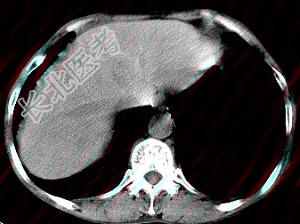

- 单项选择题男,40岁有血吸虫感染史, 腹胀不适,食欲减退, CT扫描所见如图,最可能的诊断是 ( )

A、肝炎后肝硬化

B、血吸虫后肝硬化

C、酒精性肝硬化

D、胆汁性肝硬化

E、脂肪肝